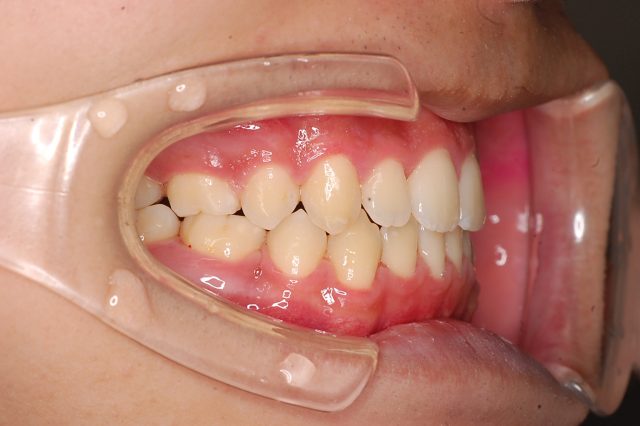

Before

After

主訴

前歯で噛めない

治療期間・回数

2年6ヶ月・30回

治療方法

マルチブラケットにて上下左右4本抜歯

費用

850000+税

デメリット・注意点

歯根吸収 歯肉退縮